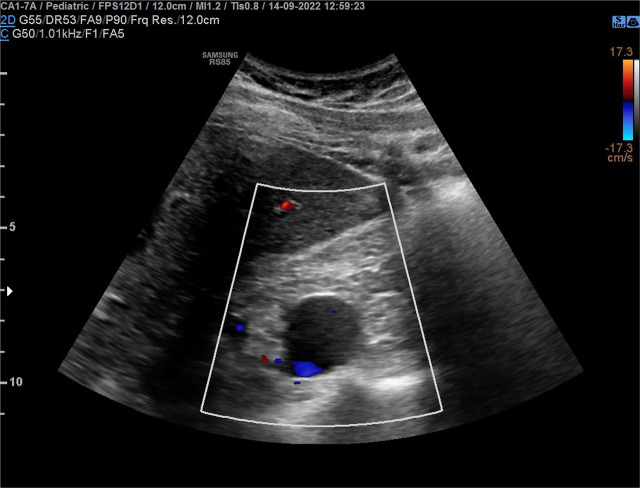

Case report: A 17-year-old boy complained of periodic abdominal pain. Abdominal ultrasonography revealed a multilocular cyst in the right kidney. Physical examination showed no abnormalities, and his blood pressure was 120/80mmHg. Abdominal ultrasonography showed a cyst measuring 36×30×25mm in the right kidney hilum. Computed tomography did not show the hepatic and suprarenal sections of the inferior vena cava. Numerous varicose-dilated collateral vessels, including renal venous vessels, were found in the right kidney hilum. The collateral vessels in the tomography matched the described in the ultrasound renal cyst. MRI confirmed IVCA with no other additional vascular abnormalities. Due to the risk of deep vein thrombosis of the lower limbs, non-pharmacological antithrombotic prophylaxis was recommended.